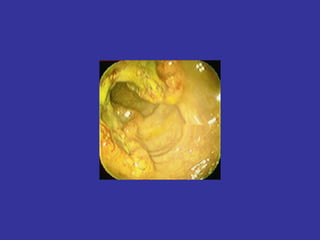

CANCER DE COLON

Cáncer+colon